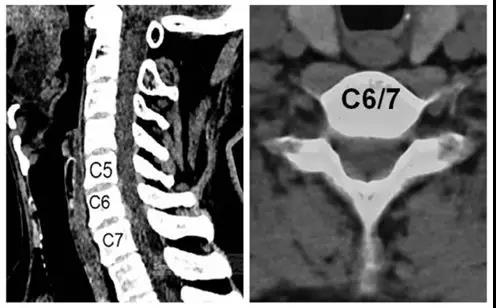

诊断:颈椎病(C6/7)

术前CT

术前核磁